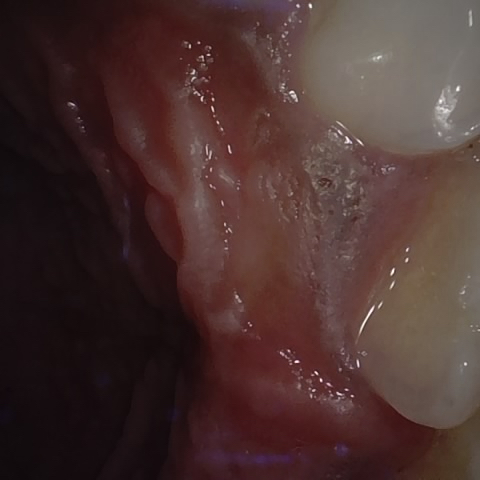

Annotated as "Good"